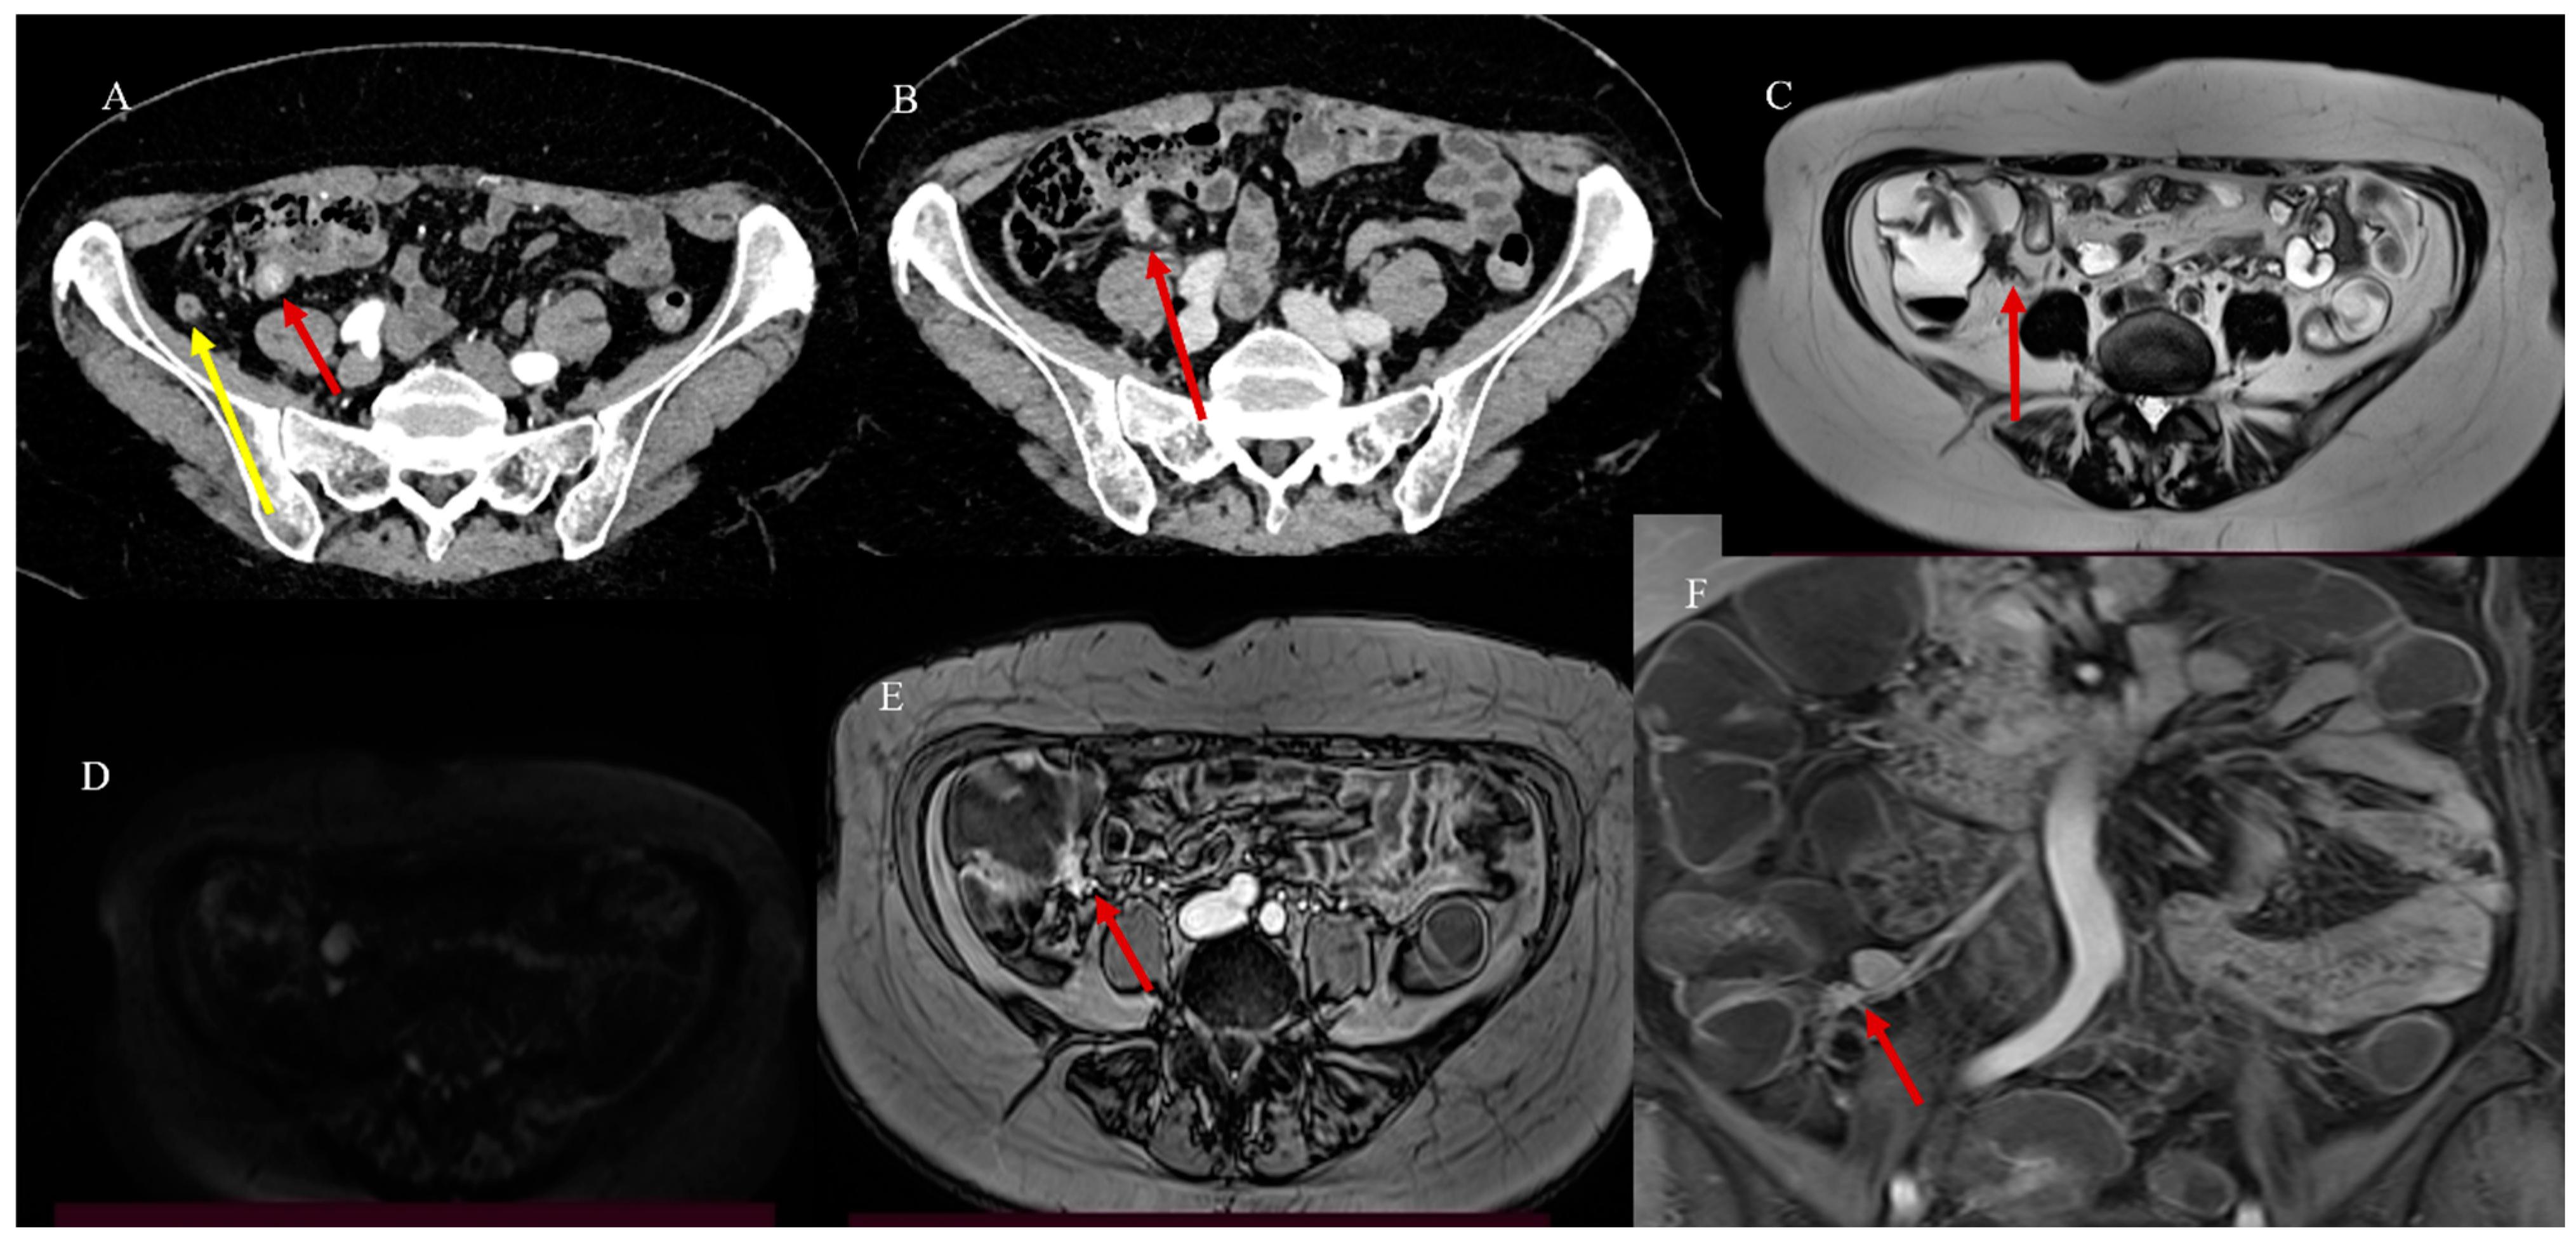

- Paparo, F.; Panvini, N.; Montale, A.; Pigati, M.; Marinaro, E.; Melani, E.F.; Piccardo, A.; Molini, L. Multimodality imaging features of small bowel cancers complicating Crohn’s disease: A pictorial review. Abdom. Radiol. 2024, 49, 2083–2097. [Google Scholar] [CrossRef]

- Pierro, A.; Minordi, L.M.; Larosa, L.; Cipri, C.; Guerri, G.; Quinto, F.; Rotondi, F.; Marcellino, A.; Basilico, R.; Iezzi, R.; et al. Small Bowel Imaging from Stepchild of Roentgenology to MR Enterography, Part II: The Reliable Disclosure of Crohn’s Disease and Non-Inflammatory Small Bowel Disorder Plot through MRI Findings. Life 2023, 13, 1836. [Google Scholar] [CrossRef]

- Masselli, G.; Casciani, E.; Polettini, E.; Laghi, F.; Gualdi, G. Magnetic resonance imaging of small bowel neoplasms. Cancer Imaging 2013, 13, 92–99. [Google Scholar] [CrossRef] [PubMed]

- Pezzella, M.; Brogna, B.; Romano, A.; Torelli, F.; Esposito, G.; Petrillo, M.; Romano, F.; Di Martino, N.; Reginelli, A.; Grassi, R. Detecting a rare composite small bowel lymphoma by Magnetic Resonance Imaging coincidentally: A case report with radiological, surgical and histopathological features. Int. J. Surg. Case Rep. 2018, 46, 50–55. [Google Scholar] [CrossRef]